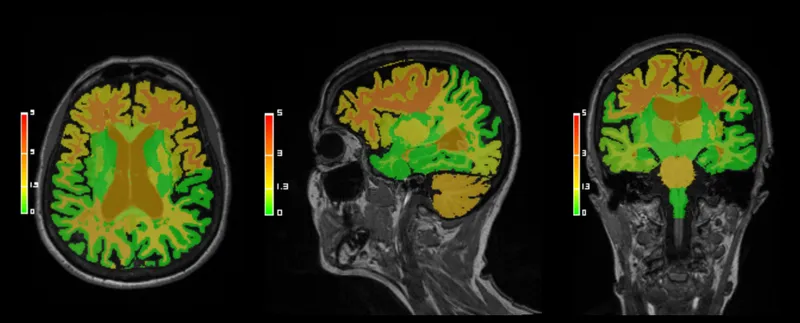

本ソフトウェアはクラウド(またはオンプレミス)環境で頭部MR画像から脳の各部位を自動的にセグメンテーションし、部位ごとの体積を自動計測します。 また白質の高信号領域の自動検出機能も備わっています。

サービスの特長

AI-Rad Companion Brain MRは後処理用の画像解析ソフトウェアで、臨床医による脳MR画像の表示、解析および評価を支援します。 以下の各種機能が備わっています。 ・各脳構造の自動セグメンテーションと定量解析 ・各脳構造の健常者集団から得た基準データとの定量比較 ・白質の高信号領域の自動検出機能 ・レポート作成のための結果表示(数値及び視覚化情報をすべて含む)